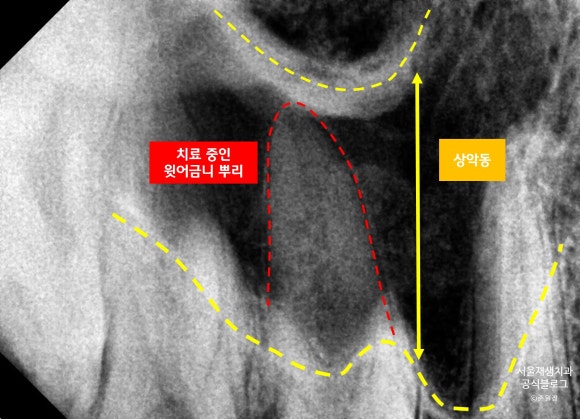

보다 이해하시기 편하도록 각 구조물들을 구분하여 표시하였습니다. 아래 사진을 참고해주세요~

하지만 위 사진을 보시면, 긴 뿌리가 잇몸뼈를 넘어서서 상악동까지 올라가고 있지요.

따라서, 뼈로 흡수되지 못한 다양한 치료 부산물을이 상악동에 고이게 됩니다.